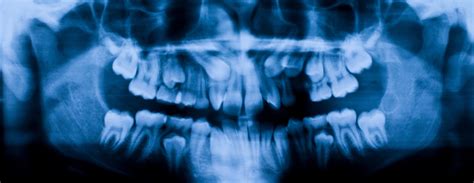

When you step into a dental office for a comprehensive examination, your dentist often suggests advanced imaging to get a complete picture of your oral health. One of the most common and vital tools in modern dentistry is the Panoramic Dental X Ray. Unlike standard bitewing or periapical X-rays that focus on one or two teeth, this imaging technique captures the entire mouth in a single, sweeping image. This includes the upper and lower jaws, all the teeth, the temporomandibular joints (TMJ), and even the surrounding sinus structures, providing a holistic view that is indispensable for accurate diagnosis and treatment planning.

The applications for Panoramic Dental X Ray imaging are vast. Orthodontists frequently use these images to map the growth of teeth in adolescents and ensure there is enough space for proper alignment. Oral surgeons rely on them to visualize the proximity of wisdom teeth to the nerves in the lower jaw, which is critical for planning extractions safely.

Furthermore, these scans are vital in diagnosing jaw joint disorders. By observing the TMJ through the panoramic image, dentists can assess if there is structural degradation or uneven wear that might be contributing to facial pain or headaches. The ability to see the sinuses is also beneficial, as it allows the dentist to distinguish between dental pain and referred pain caused by sinus congestion or infection.